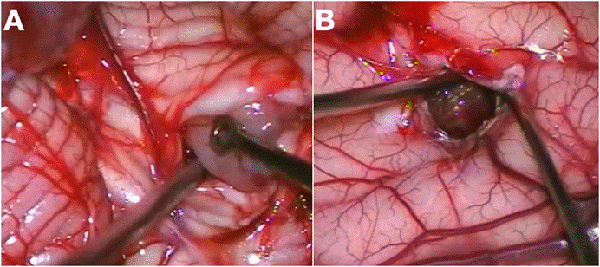

La resección parcial predominó en los grupos 1 (16 casos) y 2 (13 casos). De los 38 pacientes en los que se realizaron resecciones parciales 22 fueron lesiones supratentoriales, entre los cuales se encontraron 8 lesiones centro encefálicas (5 astrocitomas pilocíticos y pilomixoides, 1 craneofaringioma, 1 tumor embrionario indiferenciado y 1 hamartoma hipotalámico), 7 tumores de plexos coroideos (6 papilomas y 1 carcinoma de plexos coroideos) y 7 tumores hemisféricos. Por otro lado, 16 fueron lesiones infratentoriales (6 meduloblastomas, 3 teratoides rabdoides atípicos, 2 ependimomas anaplásicos, 3 astrocitomas pilocíticos, 1 pineoblastoma y 1 carcinoma de plexos coroideos). En la Figura 1 se muestran dos casos de abordajes a estos tumores.

Figura 1: Imágenes intra quirúrgicas de abordajes a tumores en SNC. A) Lesión sólido-quística cerebelosa hemisférica derecha, anatomía patológica: astrocitoma pilocítico. B) Lesión supratentorial intraventricular izquierda, anatomía patológica: papiloma de plexos coroideos.